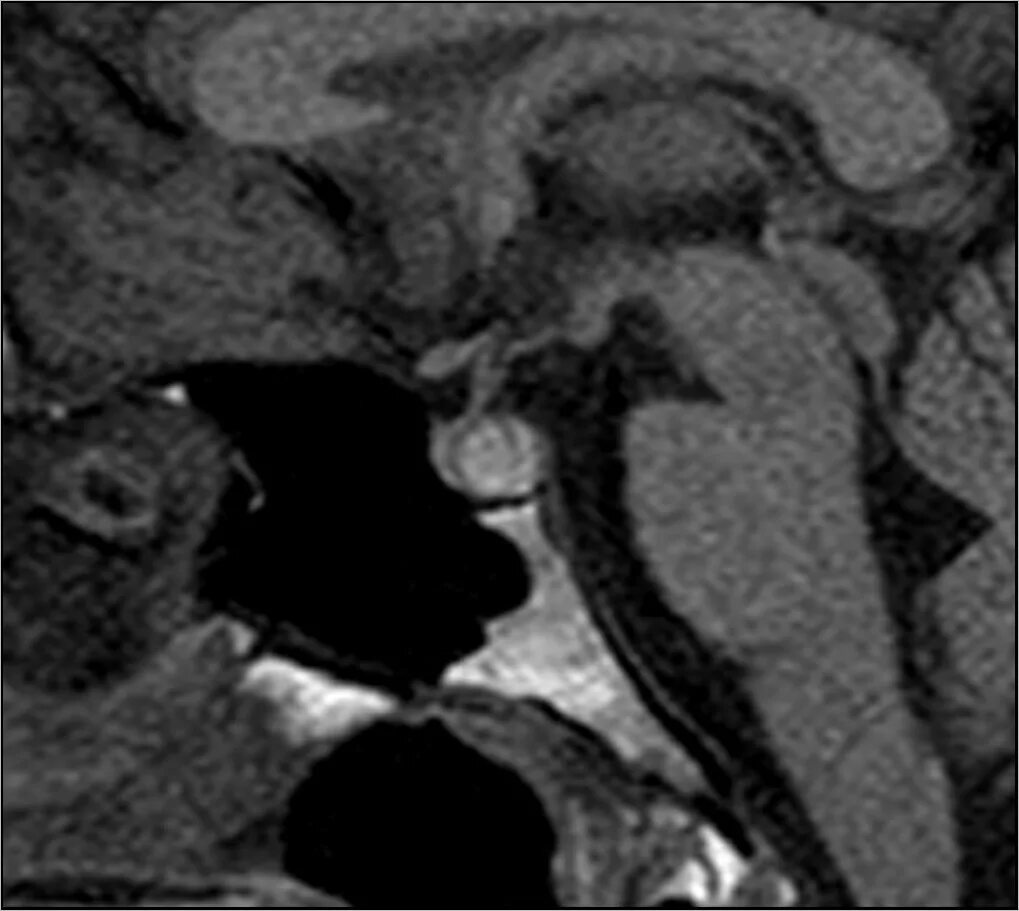

Диффузная структура гипофиза